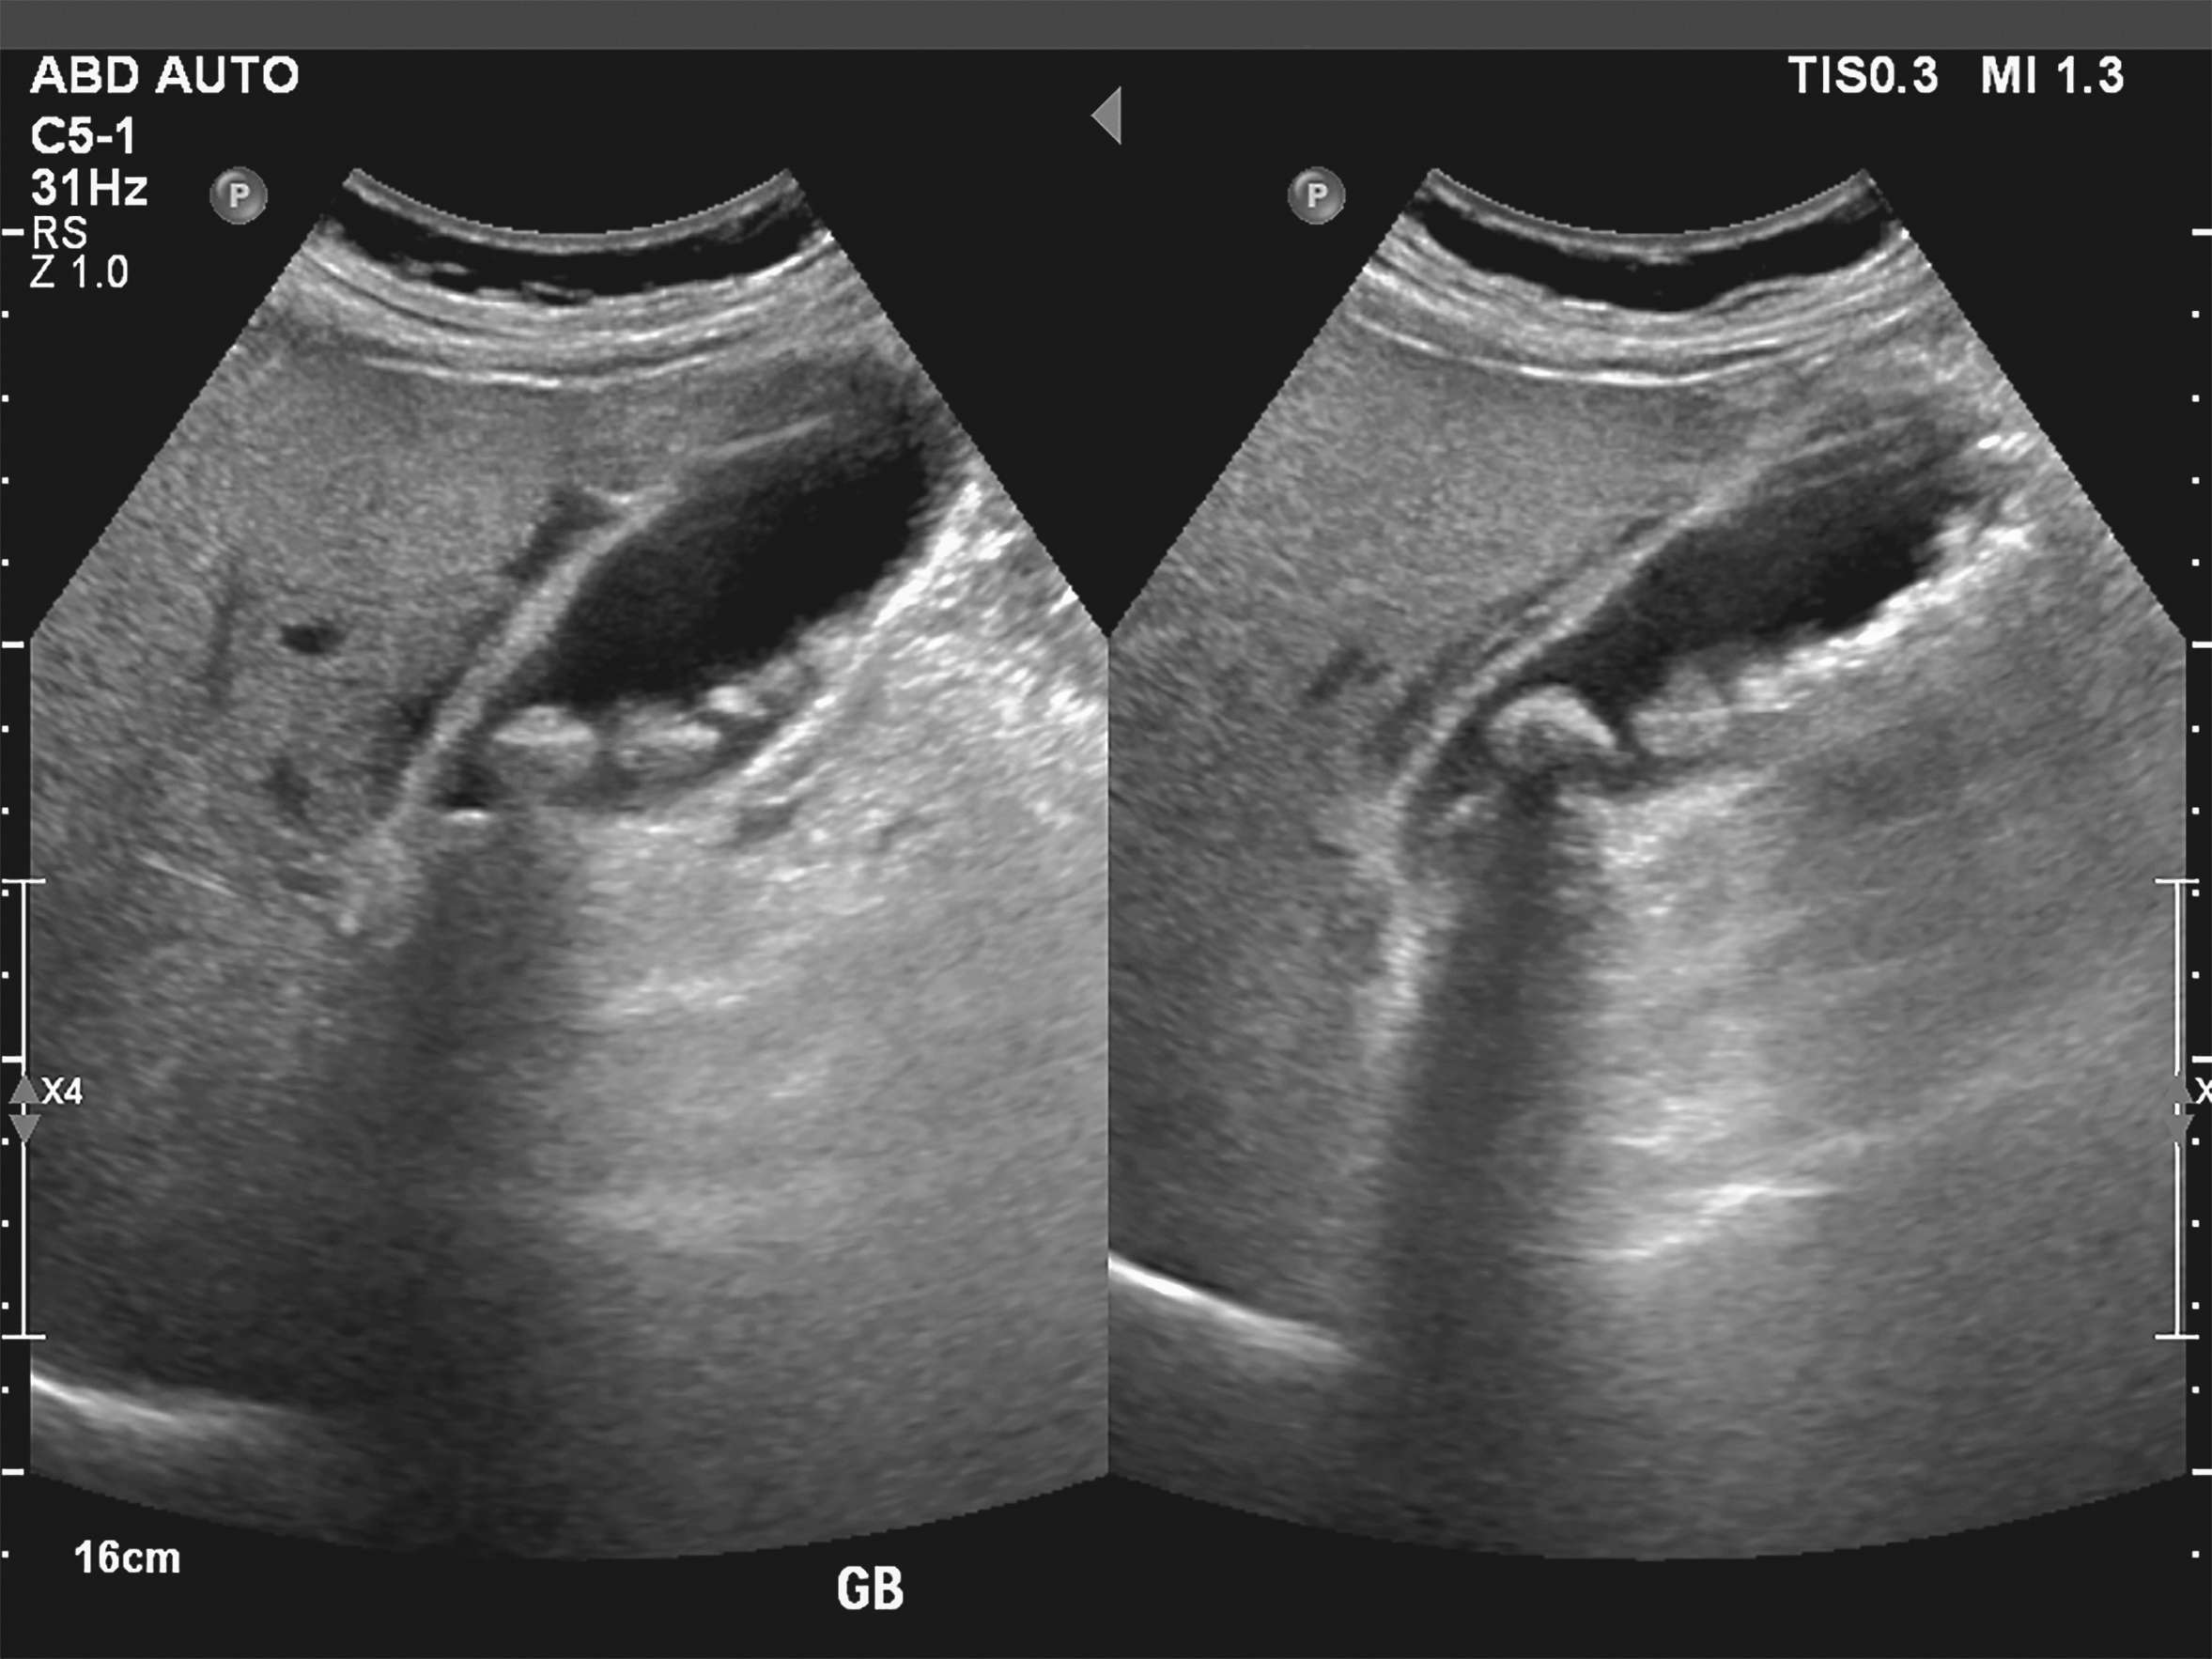

The term cholelithiasis refers to the presence of gallstones. These can occur either in the gallbladder (cholecystolithiasis), the bile ducts (choledocholithiasis) or in the small bile ducts of the liver (cholangiolithiasis). Around 10 to 15 % of the population have gallstones, although most of those affected remain symptom-free. Small gallstones are also often referred to as bile sand, sludge or gallstones.